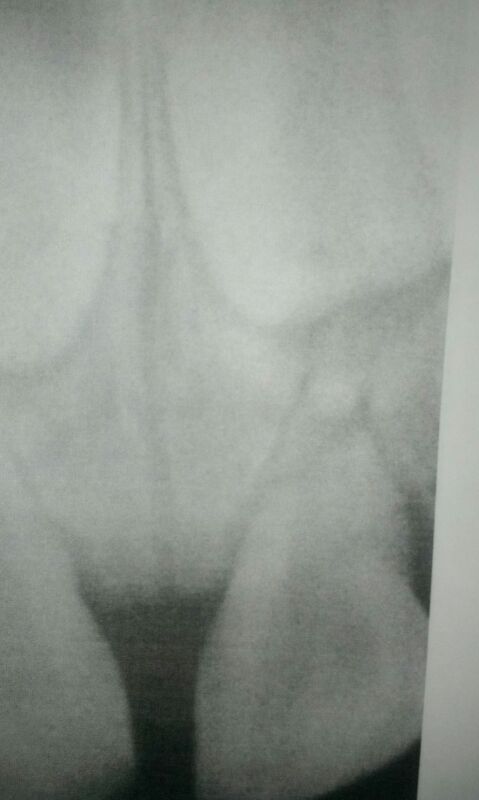

Een aantal dagen later (3) is er bij de tandarts een foto gemaakt.

De voortand blijkt bij de wortel helemaal door gebroken te zijn (zie foto).